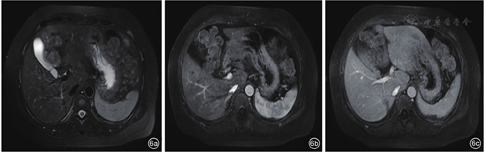

患者,女性,45岁,因糖尿病行体检无意间发现肝右叶肿物3 d入院。无腹痛、腹胀,无寒战、发热,无皮肤、巩膜黄染,无乏力,无体重减轻等。既往2型糖尿病病史,注射胰岛素治疗,血糖控制良好。无肝炎病史,无牧区居住史,无饮酒史,无肿瘤家族史。查体:体温36℃,肝、脾肋下未触及,腹平软,移动性浊音阴性。实验室检查:白细胞计数10.29×109/L,肝功能正常,乙型肝炎表面抗原和核心抗原阴性,甲胎蛋白(alpha fetoprotein,AFP)、糖类抗原19-9(carbohydrate antigen 19-9,CA19-9)及癌胚抗原(carcino-embryonic antigen,CEA)均阴性。腹部超声示:肝脏回声均匀,肝右叶被膜下探及低回声,约5.9 cm×3.6 cm,形态不规则,边界不清,周围无声晕,后方回声未见增强,内未见明显血流信号(图1)。超声诊断:肝右叶肿物,声像图不支持典型肝癌,血管源性病变待排。静脉团注2.4 ml声诺维造影剂,肝脏超声造影示:肝右叶上段可见一大小为5.3 cm×3.4 cm的弱回声团,形态不规则,超声造影呈动脉期高增强,门脉期及延迟期低增强,呈"快进快出"模式(图2)。超声造影诊断:肝右叶实性占位,倾向恶性,建议超声引导下穿刺活检明确性质。腹部CT示:肝右后叶肿物,边界不清,大小约4.1 cm×4.8 cm,分叶状,肿物密度欠均匀,平扫为低密度,增强扫描呈轻度延迟强化,病变侵犯门脉右支分支,致管腔狭窄,管壁水肿(图3),倾向炎性肉芽肿性病变,与肿瘤待鉴别,建议穿刺活检。腹部MRI示:肝右后叶肿物,范围约3.6 cm×4.8 cm,分叶状,边界不清楚,T1加权像(T1 weighted image,T1WI)低信号,T2加权压脂像(T2 weighted image/fat suppression,T2WI/FS)稍高信号影,弥散加权成像(diffusion weighted image,DWI)高信号,增强扫描轻中度延迟强化,病变侵犯门脉右支分支(图4)。腹部MRI诊断:肝右后叶肿物,考虑肝癌可能性大。临床初步诊断:肝右叶实性占位,肝癌待排。患者行超声引导下肝肿物穿刺,组织病理学回报:可见梭形细胞增生,伴炎细胞浸润,结合免疫组化,考虑炎性肌纤维母细胞性病变(图5)。免疫组化结果显示:AE1/AE3(-),Vimentin(3+),Actin(1+),SMA(2+),Desmin(-),s-100(-),CD1a(-),CD21(-),CD35(-),CD68(3+),Ki-67(10%)。患者定期复查,未行治疗。5个月后复查腹部MRI示:原肝右后叶肿物,现已显示不明确,仅局部可见小片状异常信号,T1WI低信号,T2WI/FS低信号,DWI无明显扩散受限,增强扫描强化程度低于周围肝实质(图6),符合良性病变,请结合临床及病理。结合既往穿刺活检及影像学随访病灶消退病史,患者最终诊断为肝脏炎性肌纤维母细胞瘤。随访至今21个月,患者一般情况良好,无复发。

HIMT的治疗方式包括手术、应用大剂量类固醇激素和非甾体类抗炎药及保守观察等。有学者倾向于推荐肝切除手术,认为其更适用于手术低风险患者[3]。考虑到肝脏手术创伤大、术后存在一定并发症,有学者提出不同看法。国内李明信等[7]分析近1000例HIMT病例后认为,对于肿瘤位于肝门部、手术风险大、切除困难者,推荐观察或保守治疗。一项多中心研究发现,27例HIMT经保守治疗后肿瘤可缩小,甚至完全消失[6]。Sarrami等[17]认为,HIMT保守治疗效果好,也可能自行缓解,因此在行穿刺活检排除恶性肿瘤后,观察随访或保守治疗应当成为治疗首选。而对于诊断不明确、保守治疗无效或发生严重并发症的患者,可考虑手术切除[18]。有研究认为,肝脏病灶在重复影像学检查中自行消退的特点对准确诊断HIMT具有重要意义[15]。近年有学者[19]报道,1例以发热为首发症状的多灶肝占位患者,腹部MRI及全身PET-CT检查结果均倾向转移瘤,而肝脏穿刺未发现恶性证据,故未治疗仅进行影像学检查随访,1个月后肿瘤完全消失,最终结合病史、影像学表现及转归,该患者诊断为HIMT,并且研究者推荐可将严密观察作为HIMT的处理方式。结合本例患者肿瘤自愈的特点,进而推测严密影像学随访可能使HIMT患者获益。